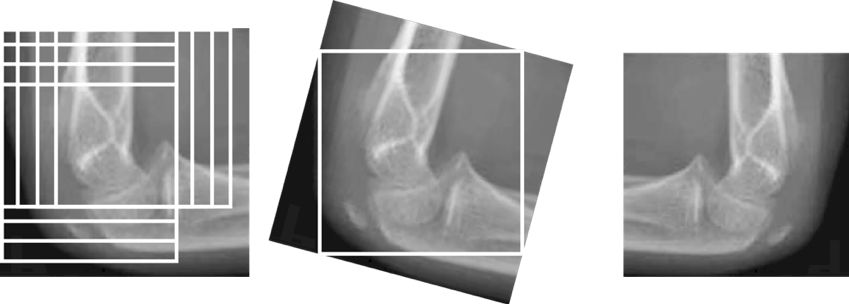

Since the researchers lacked the number of X-ray images, it was difficult to cope with the various cases where the actual data were input, so the reference images were enlarged using clipping, inversion, and rotation. The process of extension was performed as follows. Moving and cutting vertically and horizontally at every 10 pixels were performed and rotated 15 degrees and left and right reversed images were used as images for inputting a total of 576 images into the neural network. As a result, the study was conducted as shown in Fig. 3, and a image based on the standard age was used as the learning data, and the image with the label and the image without the learning were used as the validation data.

Refer to caption

Figure 3: Image Augmentation